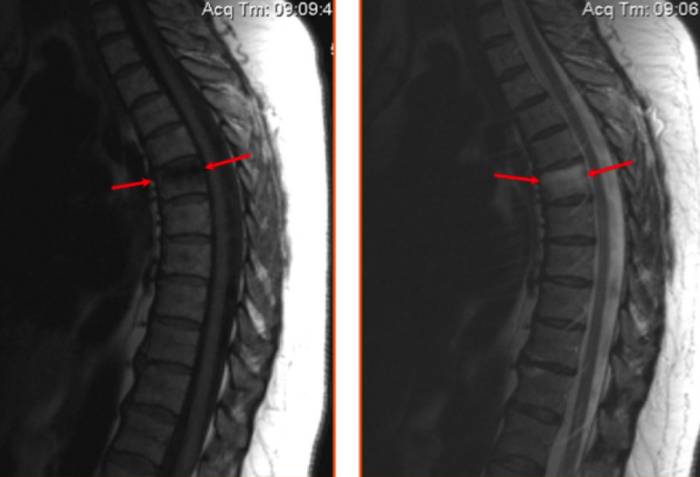

На снимке МРТ представлен поясничный остеохондроз, стрелками обозначен пораженный диск с формированием спондилодисцита

На МР-изображении стрелками показан ушиб шестого грудного позвонка (визуализируется отек костных структур без деформации тела позвонка)